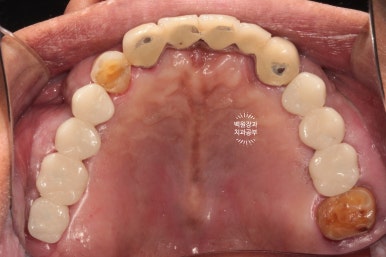

처음 오셨을 때의 상태입니다.

엑스레이를 같이 참고해 보셔야 하는데요,

양쪽 위 큰 어금니가 모두 발치된 상태로 오래 지내신 분이었어요.

보시면 상대적으로 아래 앞니가 머리가 매우 조금만 남아있는 것을 보실 수 있으실텐데요,

아래 앞니가 저렇게까지 극적으로 사라지게 된 경위를 살펴보자니

위 어금니가 없는채로 오래 지내시다보니

주로 앞니로 식사를 하게 됩니다.

위 앞니는 금속-도재 고정성보철물(PFM bridge)로 제작이 되어있는데요, 도재가 씌워진 보철물에 의해 아래 앞니의 마모가 가속화되고

결국 아래 앞니의 머리가 없어질때까지 깨지고 닳고.. 그런 과정을 거치게 된 것이죠.

대구치의 상실은 교합의 붕괴에 가장 큰 영향을 주는 것 같습니다.

아래 앞니의 마모도가 상당히 심합니다.

치과에서 교모(attrition)라고도 하는데요, 머리가 닳아 없어지다보니 치아 내부의 신경관이 드러나게 되고

그렇게 발생한 치통을 해결하기 위해 신경치료를 모두 받으셨던 흔적도 보여요.

여튼.. 심각합니다. 치료가 시급한 상태셨어요.